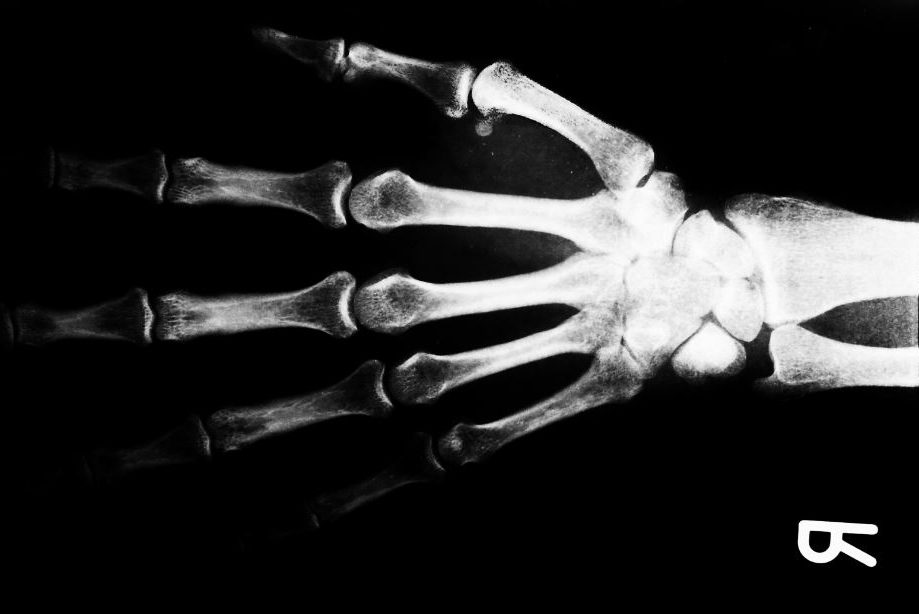

MANNHEIM. Ein Kleintransporter voller Experimente soll Schülern die Röntgentechnologie näherbringen und sie für Naturwissenschaften begeistern. Im Zuge eines Projekts anlässlich des «Röntgenjahres» 2020 können Besucher mit einem Ultraschallgerät ein Gallenblasen-Modell durchleuchten, Schnittbilder eines Frosches anfertigen oder die Radioaktivität verschiedener Stoffe messen.

Mit dem Angebot an Schulen in ganz Deutschland feiern die Mannheimer Reiss-Engelhorn-Museen (rem) und das Deutsche Röntgen-Museum Remscheid die Entdeckung der Röntgenstrahlung vor 125 Jahren und den Geburtstag ihres Entdeckers Wilhelm Conrad Röntgen (1845-1923) vor 175 Jahren. Der erste Nobelpreisträger für Physik legte die Basis für die vielfältige Anwendung der nach ihm benannten Strahlen – sei es die Computertomografie, die Suche nach Menschen mit Wärmebildkameras oder die Durchleuchtung von Gepäckstücken.